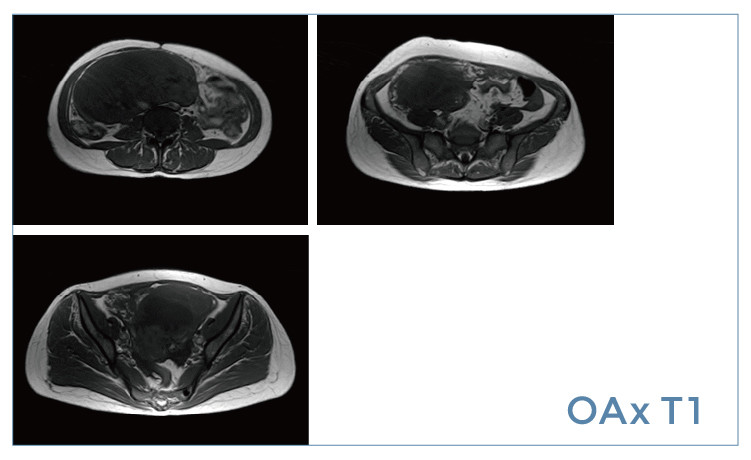

【朗润影像档案】20190412磁共振影像病例结果讨论

【朗润影像档案】磁共振影像病例分享(编号20190412)